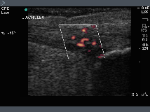

Achilles Tendon: Intrasubstance tearing acute power doppler activity